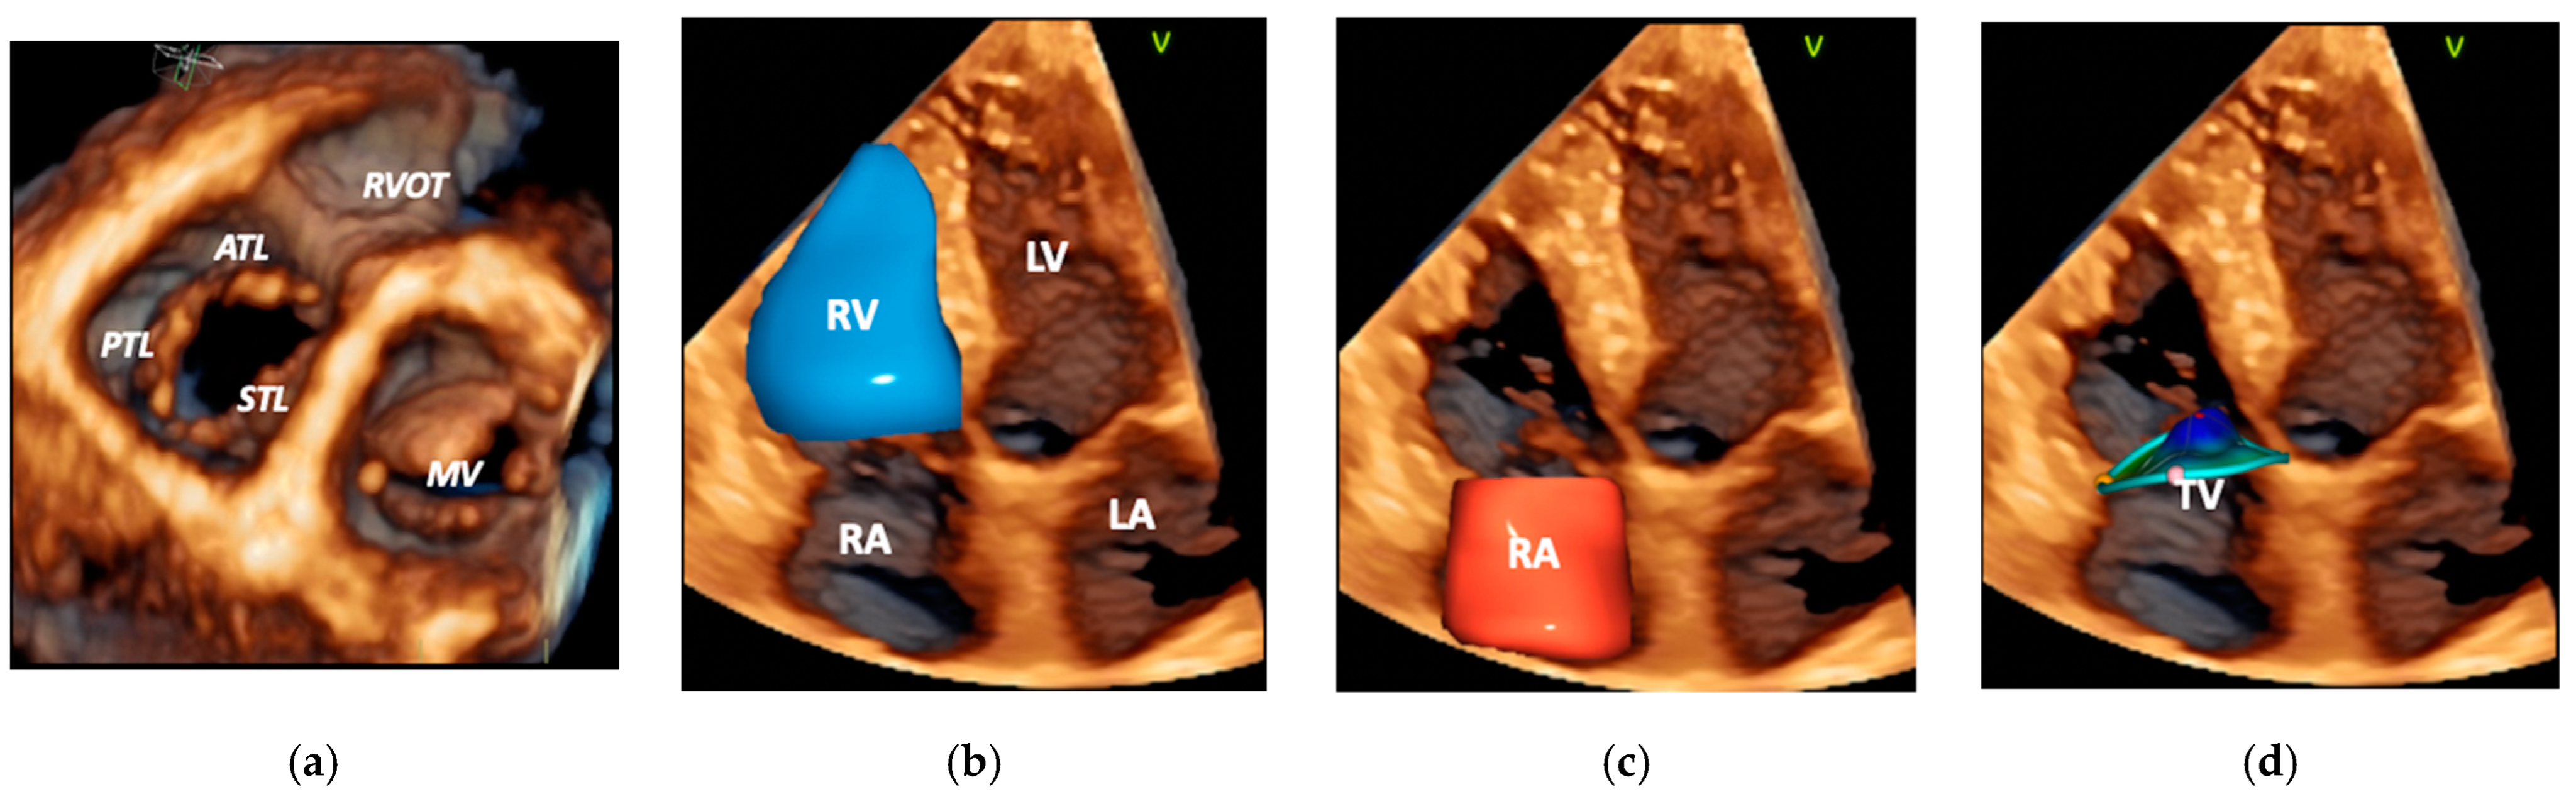

2. Anatomy and Pathophysiology of A-FTR

3.1. Echocardiography